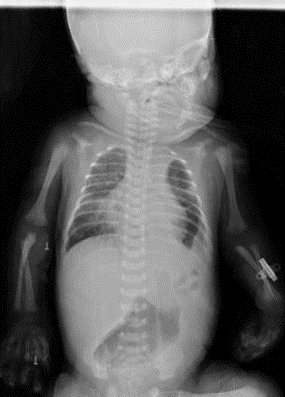

Male newborn, 36.4 weeks by last menstrual period, Apgar 5 -7T, weight 2,570 grams, ORH+. No significant maternal history, normal prenatal ultrasounds. Born in a second- level hospital, presenting with acute respiratory distress, requiring advanced neonatal resuscitation with positive pressure ventilation and orotracheal intubation. Transferred to our hospital where the presence of left diaphragmatic hernia associated with respiratory insufficiency, shock, perinatal asphyxia, and seizures was determined. Admitted to the neonatal intensive care unit in the following conditions: Hypotonic, flaccid, hyporeactive pupils with diminished brainstem reflexes, oro-intubated, shock score 4 points, and on vasoactive drugs. Chest X-ray showed the presence of intestinal loops in the left hemithorax, signs of left pulmonary hypoplasia (figure 1);

Figure 1 AP Chest X-ray

Opacification of left hemithorax and contralateral cardiac displacement

Source: Hospital de Especialidades de las Fuerzas Armadas N°1